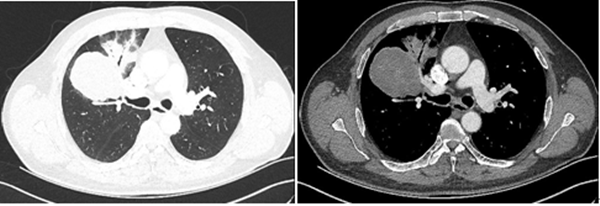

患者肿瘤位于右肺上叶,直径约10cm,与肺血管关系密切,粘连紧密,手术难度高,风险大。入院后,胸外科主任李少民教授查看患者,阅读影像资料,向家属沟通病情及治疗方案。治疗团队决定行单操作孔胸腔镜下右肺上叶切除术,完善术前准备后,李少民教授带领手术团队在麻醉科及手术室的配合下,历时2小时余,成功完成了单操作孔胸腔镜下右肺上叶切除及纵隔淋巴结清扫术,患者术后恢复良好,胸部仅可见两处切口,长度分别为1cm、5cm,大大减轻了患者的创伤,有利于术后的快速康复。